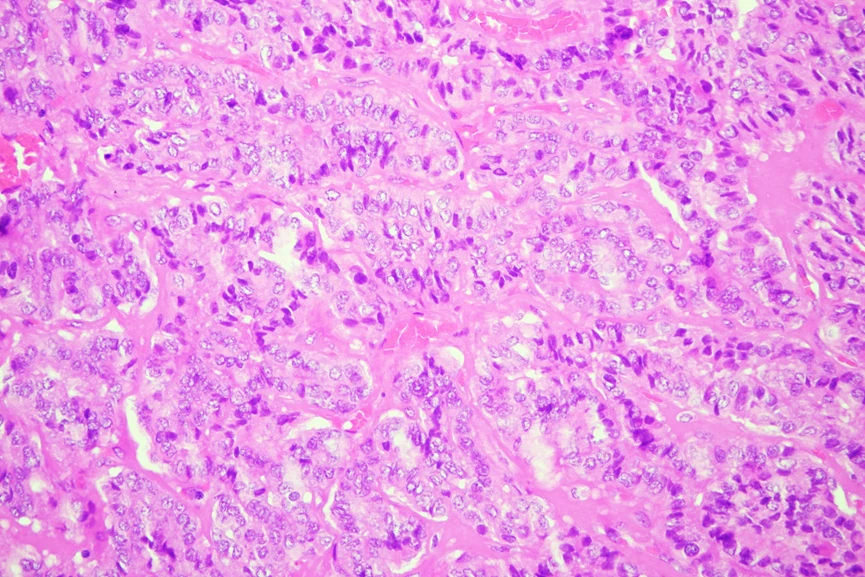

3. ¿Qué características histológicas se deben investigar intencionadamente dentro de esta lesión?

a) Componente sarcomatoso

b) Conteo mitósico

c) Áreas insulares

d) Núcleos en vidrio esmerilado, inclusiones citoplasmáticas

e) Todas las anteriores